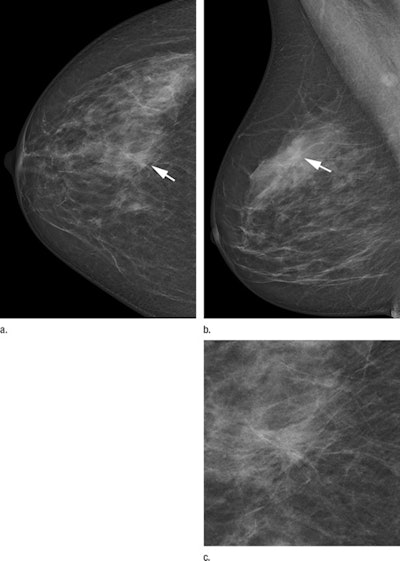

The findings echo previous studies that found an increase in the detection of microcalcifications with photon-counting mammography and, thus, higher rates of DCIS detection. The authors posited that the higher spatial resolution of photon-counting mammography, with a pixel pitch of 50 microns versus 70 microns for DR-based conventional mammography, could account for the difference, as DCIS tends to be depicted by calcifications.

Photon-counting mammography also showed a higher rate of DCIS detection than conventional digital mammography, at 0.23% versus 0.12% (p < 0.05), and a higher proportion of DCIS compared to all screening-detected malignancies, at 29.2% versus 20.7% (p = 0.01).